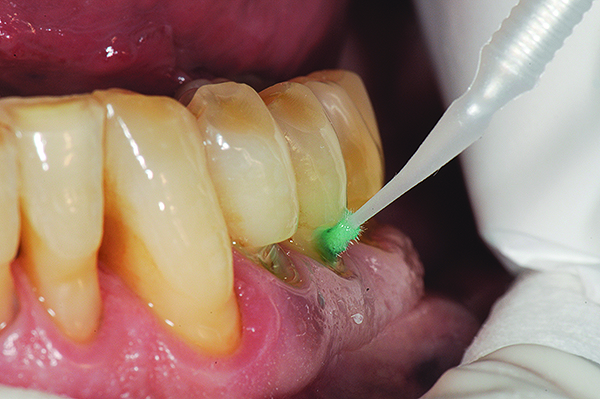

Fig 7. Cavities were cleaned with 20% polyacrylic acid solution.

Figure 7